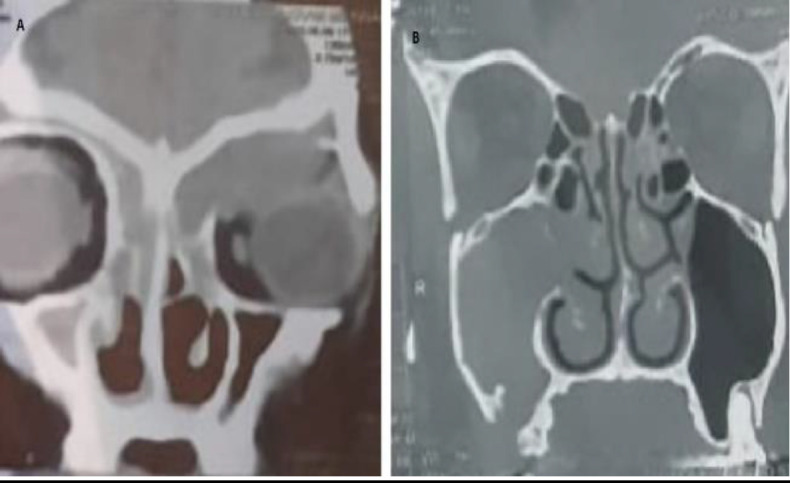

Results: In pediatric patients, the most common inflammatory pathology was antrochoanal polyps, followed by allergic fungal sinusitis. On the other hand, chronic sinusitis without nasal polyps is the most common in adults, followed by antrochoanal polyps. The mean duration of clinical manifestations before diagnosis in pediatric patients was significantly shorter than that in adults (P=0.001). The most common symptoms in both pediatric and adult patients were anterior nasal discharge and nasal obstruction. Proptosis was significantly higher in pediatric group than in adult group (P=0.015). On computed tomography (CT), the most commonly affected sinus in both pediatric and adult patients was the maxillary sinus followed by the anterior ethmoid sinus. Bone expansion, erosion and involvement of adjacent structures were significantly higher in pediatric patients (P=0.028, 0.027 respectively).

Conclusion: Pediatric patients have a high incidence of antrochoanal polyps and allergic fungal sinusitis as unilateral inflammatory lesions. These lesions require surgical management. Inflammatory paranasal sinus lesions in pediatric patients have a shorter duration of clinical manifestations and a higher incidence of bone erosion and involvement of adjacent structures; therefore, early diagnosis and management prevent complications.